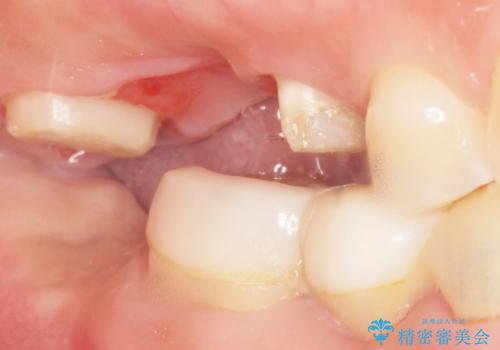

奥歯2本(右上76)はう蝕が深く保存不可能な状態であったため、やむなく抜歯しました。

インプラントも入れ歯も抵抗があるとのご相談により、自家歯牙移植を提案しました。

使っていない親知らず(右上8)を右上7抜歯窩に移植し、支台歯としてブリッジによる補綴治療を行いました。